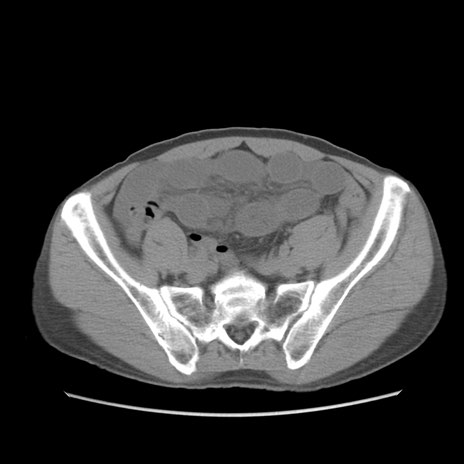

症例56 CT(横断像)

脂肪ウインドウ